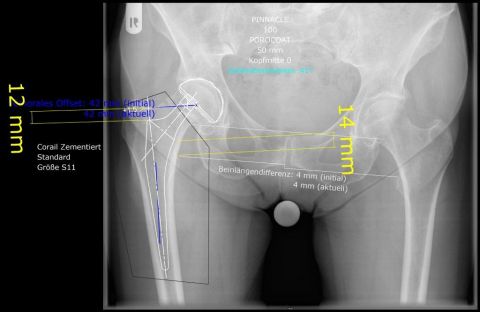

03/2021 – 76 jährige Frau mit wahrscheinlich durch Osteoporose bedingtem Bruch des Schenkelhalses rechts. Es wurde ein zementierter Standardschaft verwendet, der eine gleichmäßige Krafteinleitung in den Knochen des Oberschenkels gewährleistet.  Verlauf sonst unkompliziert mit guter Gelenkfunktion bereits 2 Monate nach Operation. Die Osteoporose sollte durch Bewegung und Medikamente über einen längeren Zeitraum behandelt werden.

OPERATIVE VERSORGUNG DER PATIENTIN

Planung der Hüftendoprothese